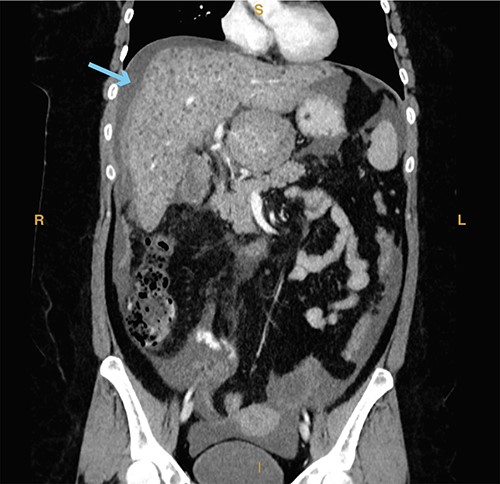

A 23-year-old woman with a past medical history of autoimmune hepatitis with ascites on azathioprine and prednisone presented from an outside hospital with 24-hour acute onset of worsening right upper quadrant pain and mild nausea. Patient’s model for end-stage liver disease score based on an INR value from 3 months prior is 14. Prior to being transferred to our emergency department, the patient was hypotensive (systolic blood pressure of 90 mm Hg) and given crystalloid resuscitation. Initial workup revealed a hemoglobin of 8.9 g/dl, a hematocrit of 25.8%, elevated lactic acid to 2.7 mmol/l (normal range 0.3–1.9 mmol/l) and elevated total bilirubin of 2.4 mg/dl (normal range 0.3–1.2 mg/dl). Computed tomography of the abdomen and pelvis revealed significant hemoperitoneum with suspected gallbladder perforation, as well as small calculi in the gallbladder neck (Fig. 5).

Computed tomography imaging from Case 3 showing significant hemoperitoneum (cyan arrow). Present in the figure, the letters S, L, I and R denote superior, left, inferior and right respectively.

On exam, the patient was in mild discomfort with some pain localized to the right upper quadrant without rebound or guarding. However, in the setting hemodynamic instability for which the patient received 2 units of packed red blood cells in the emergency department, downtrending hemoglobin and radiographic findings of hemoperitoneum, the decision was made for urgent surgical intervention despite poor liver reserve due to patient’s Child-Pugh class B cirrhosis.